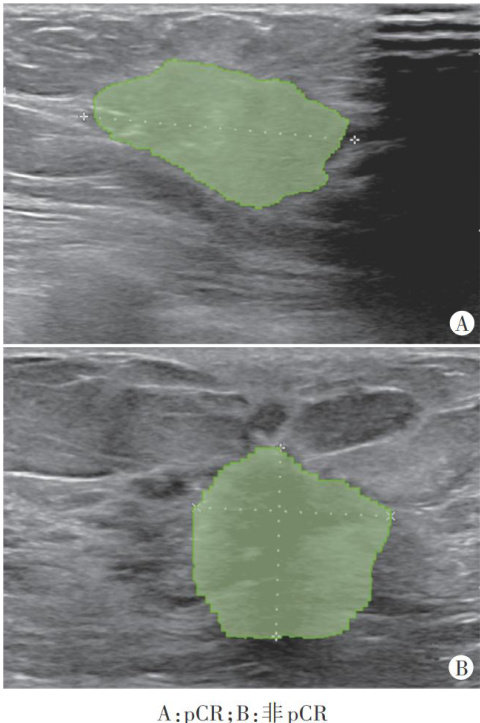

摘要目的 探讨斑点追踪技术(STI)评估射血分数中间值心力衰竭(HFmrEF)患者左室心肌功能的临床价值。方法选取我院心血管内科慢性心力衰竭患者195例,根据左室射血分数(LVEF)分为射血分数减低心力衰竭(HFrEF)组 LVEF<40% )HFmrEF组 40%?LVEF?49% 及射血分数保留心力衰竭(HFpEF)组 (LVEF?50% ,应用STI检测左室心肌功能参数,包括整体纵向应变(GLS)、峰值应变离散度(PSD)整体做功指数(GWI)、整体做功效率(GWE),比较各组上述参数的差异。分析STI参数与LVEF的相关性。绘制受试者工作特征(ROC)曲线分析STI参数鉴别HFmrEF与HFrEF、HFmrEF与HFpEF的诊断效能。结果HFpEF组、HFmrEF组、HFrEF组GLS、GWI、GWE均依次降低,组间两两比较差异均有统计学意义(均 P<0.05 );HFrEF组PSD明显增大,与HFmrEF组和HFpEF组比较差异均有统计学意义(均 P<0.05 );HFmrEF组与HFpEF组PSD比较差异无统计学意义。相关性分析显示,GLS、GWI、GWE均与LVEF呈正相关 (r=0.85,0.74,0.72 ,均 P<0.001 ),PSD与LVEF呈负相关 (r=-0.30,P<0.001) 。ROC曲线分析显示,GLS、PSD、GWI及GWE截断值分别为

时鉴别HFmrEF与HFrEF的曲线下面积为0.938、0.676、0.890、0.885;GLS、GWI及GWE截断值分别为 -11.35%,1428.5mmHg%?87.50% 时鉴别HFmrEF与HFpEF的曲线下面积为0.929、0.877、0.866。结论STI可精准评估HFmrEF患者左室心肌功能,为其独立分型管理提供影像学依据。